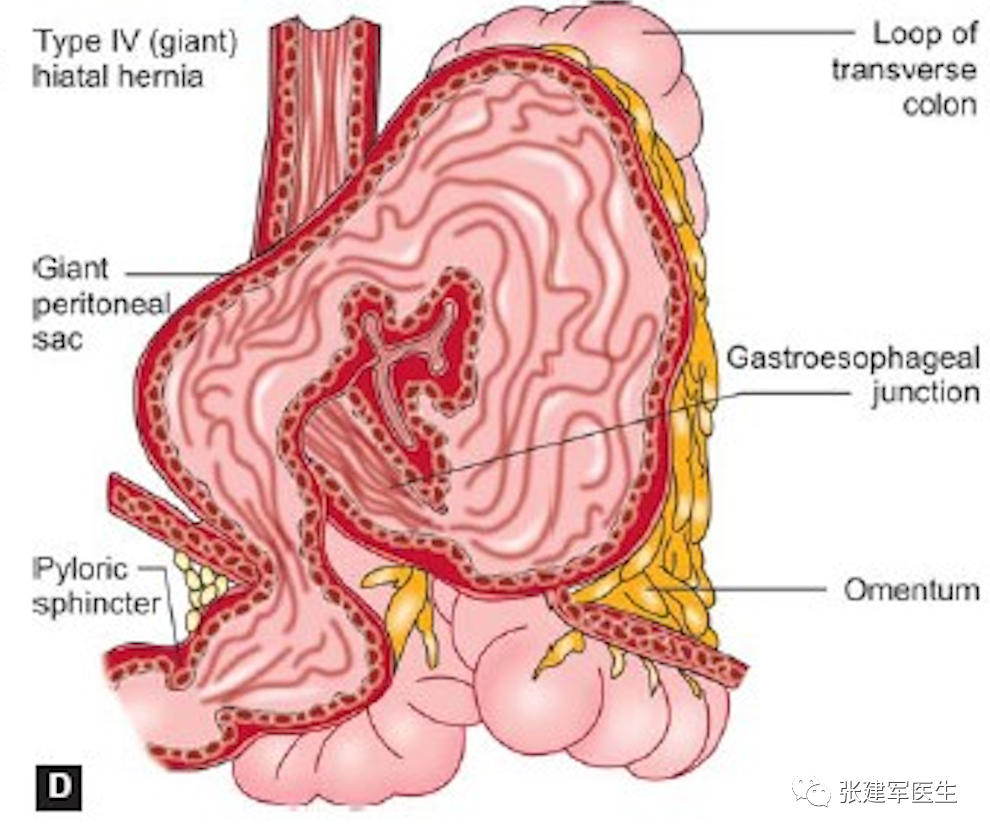

食管裂孔疝主要有两种类型:滑动性食管裂孔疝和食管旁食管裂孔疝。大多数为滑动型食管裂孔疝,即1 型。其他三种类型均为食管旁疝。

IV型食管裂孔疝 除了胃之外,腹腔内其它脏器如脾脏、部分结肠、网膜等也通过食管裂孔疝入胸腔。